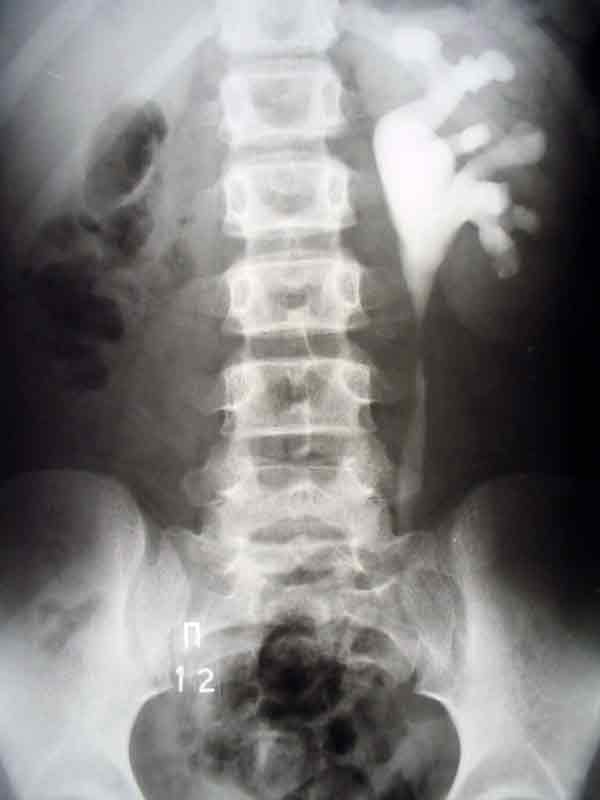

Гидронефроз. Диагностирование и лечение гидронефроза.

Заболевание гидронефроз относится к урологическим болезням. Под гидронефрозом в медицине понимают дисфункцию почки, связанную с расширением ее чашечек и лоханки и прогрессирующим истончением почечной ткани. Причина развития гидронефроза – нарушение оттока мочи из почек, как правило, гидронефроз является следствием или осложнением некоторых других заболеваний.

Диагностирование заболевание требует УЗИ почек и осмотра у квалифицированного уролога. Симптоматика гидронефроза размыта, это могут быть боли в спине, кровь при мочеиспускании). Медицинский центр «Твой Доктор» предлагает комплексное обследование мочевыводящих путей – УЗИ почек, доплерография сосудов почек, рентгеновские исследования, различные лабораторные анализы. Собственная лаборатория медцентра позволяет быстро и качественно провести лабораторную диагностику заболевания с последующим лечением.